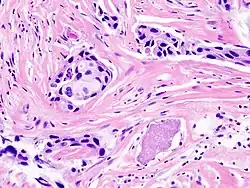

![]() skirhotický intraduktální karcinom | |